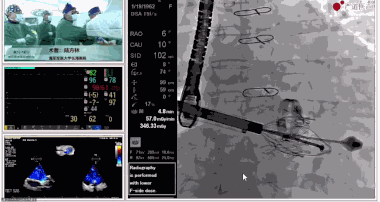

陸方林教授分享的是一例極重度三尖瓣返流的患者采用健世科技(LuX-Valve®)經(jīng)導(dǎo)管三尖瓣置換系統(tǒng)進(jìn)行的手術(shù)直播演示。此例患者為69歲女性,入院前17年行二尖瓣機(jī)械瓣置換術(shù),術(shù)后長期服用華法林抗凝,既往“2型糖尿病”病史5年,“雙下肢水腫”3年。3個(gè)月前患者出現(xiàn)腹脹、雙下肢水腫,伴活動(dòng)后暈厥,伴黃疽、皮膚濕癢、牙齦出血,癥狀持續(xù)加重,遂入院治療。入院后行心臟CT、心臟超聲檢查,提示:“三尖瓣關(guān)閉不全(極重度),二尖瓣置換術(shù)后,心功能III級”。徐志云、陸方林微創(chuàng)三尖瓣置換團(tuán)隊(duì)對該患者的病情進(jìn)行了充分的評估和討論。由于患者有開胸二尖瓣置換手術(shù)史,且病史時(shí)間長,同時(shí)存在相關(guān)合并癥,傳統(tǒng)外科手術(shù)風(fēng)險(xiǎn)極高(STS評分:8.315%),最終決定采用三尖瓣LuX-Valve®瓣膜系統(tǒng)對患者進(jìn)行治療。

▲瓣膜植入前右心室造影

▲瓣膜植入過程

▲瓣膜植入后釋放的過程

▲瓣膜植入后右心室造影

在手術(shù)直播中瓣膜植入過程不到10分鐘,手術(shù)獲得圓滿成功,充分體現(xiàn)徐志云、陸方林團(tuán)隊(duì)技術(shù)精湛,團(tuán)隊(duì)協(xié)作默契及器械的優(yōu)越性。